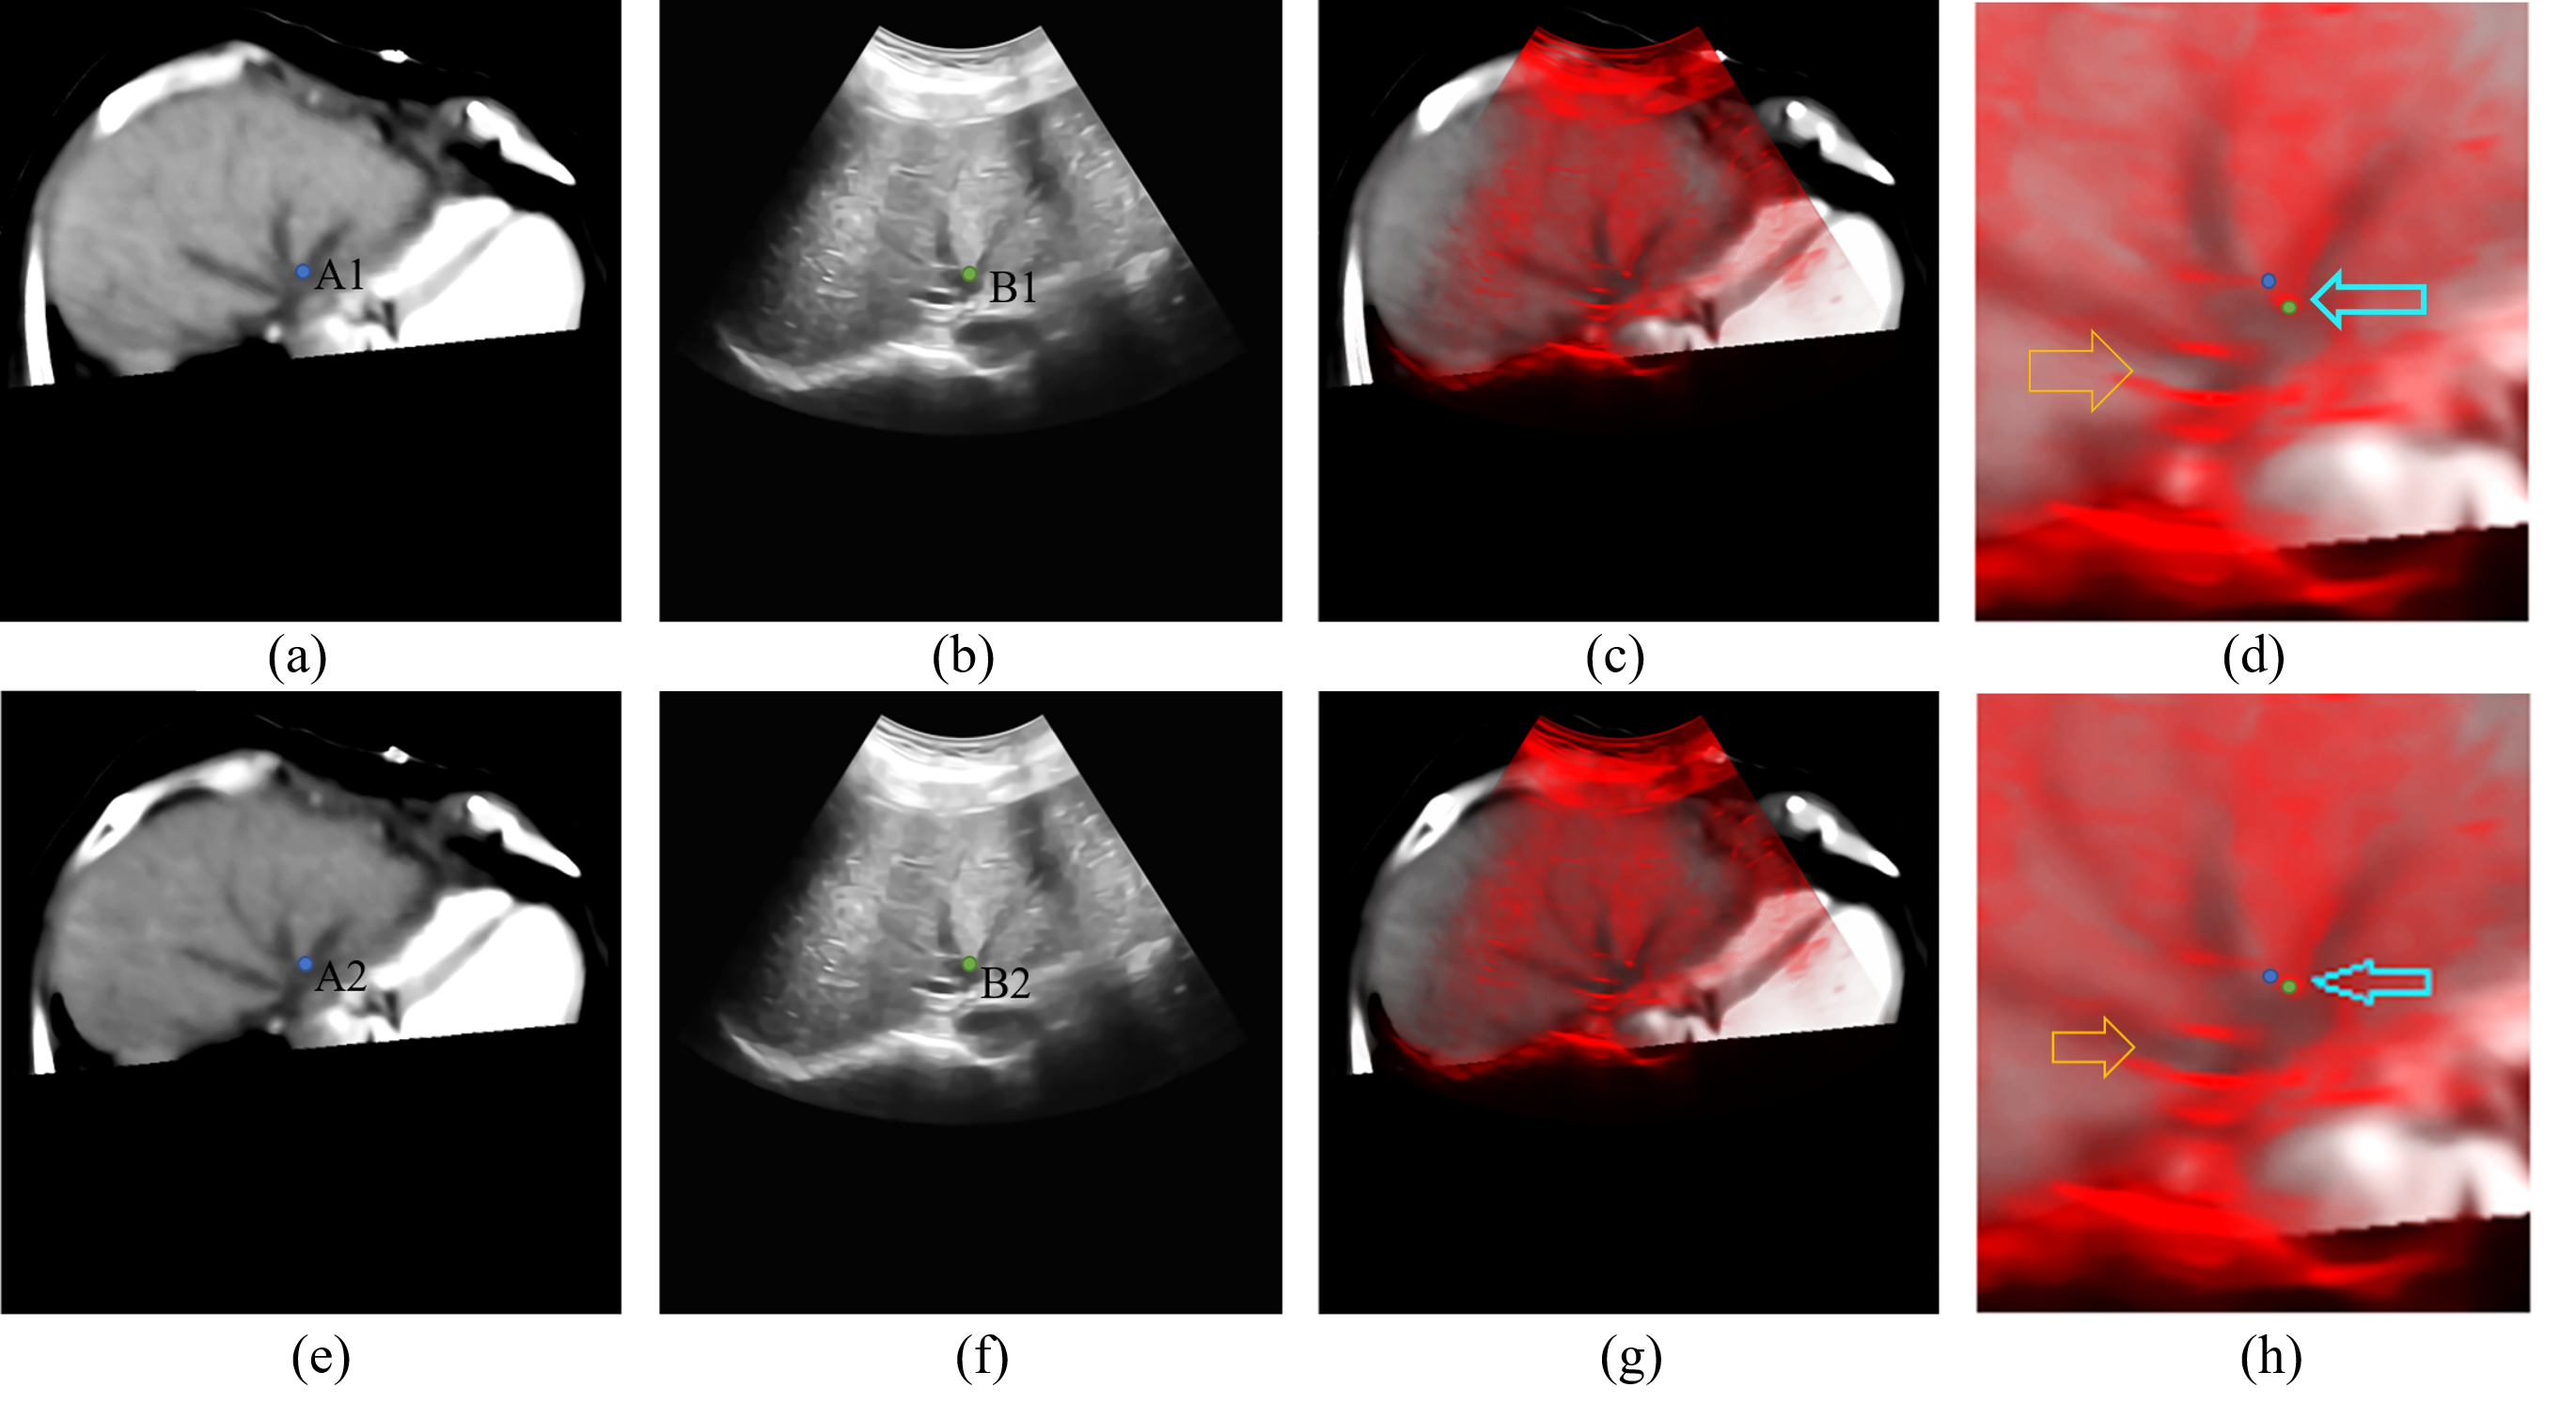

Figure 3: The data before and after registration of test 1. (a) is the corresponding CT slice of the original ultrasonic image (b) after the matching of world coordinate system. (e) is the result of the rigid registration from CT volume data to ultrasonic image. (f) is the non-rigid registration result of the ultrasonic image (b). (c) and (g) are the fusion image of (a) (b) and (e) (f), (d) and (h) are the details of (c) and (g), respectively.

The data before and after the registration are shown in Fig. 3-5, where subfigures 3(a), 4(a) and 5(a) are CT slices corresponding to original ultrasonic images, subfigures 3(b), 4(b) and 5(b) after the matching of the world coordinate system. Subfigures 3(e), 4(e) and 5(e) are CT slices after rigid registration to original ultrasonic images, and subfigures 3(f), 4(f) and 5(f) are non-rigid registration results of original ultrasonic images to their correspondence rigid registered CT slices. And fusion images of CT slices and ultrasonic images before and after registration are obtained and shown in Figs. 3(c) – 5(c) and 3(f) – 5(f) to better evaluate our algorithm. According to these figures, on comparison with the fusion image before registration, boundaries of both the liver and vessels are better matched. And the positions and shapes of vessels are also corrected. And the positions of bones in Figs. 4(g) and 5(g) are also closer to their positions in the ultrasonic images, which can be inferred by their “shadows” in the ultrasonic image.

The details of results in Figs. 3-5 are shown in subfigures (g) and (h) of Figs. 3-5, which also show that our registration algorithm can improve the matching accuracy between the CT data and ultrasonic images, especially in the parts pointed by arrows in Figs. 3 and 4. However, although our algorithm has better registration performances than the Demons algorithm, there still exists some parts that can be improved, such as the places pointed by the blue arrow in Fig. 4(h) although the distance between points A2 and B2 is shorter than that between points A1 and B1, points A2 and B2 are still not matched.